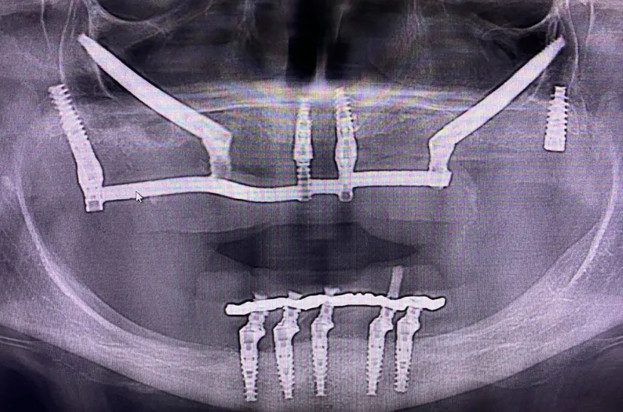

Спочатку на місце видалених зубів у кістку або під окістя впроваджується тверда конструкція (штучний корінь) – відбувається безпосередньо імплантація. Потім формуються ясна, встановлюється абатмент – елемент імпланту, що розташовується над ясенною поверхнею, що є сполучною ланкою між стрижнем і протезом. І останнім виступає протезування – установка на каркас ортопедичних конструкцій, що замінює верхівку зубної одиниці.

Далі настає хірургічний етап (трохи більше години) з допомогою малоінвазивних методів. До кісткової тканини доступ виходить одразу після екстракції зубної одиниці, потім лунка розширюється та встановлюється імплант. При цьому абатмент повною мірою не занурений під слизову оболонку, а трохи виступає над ясенним краєм. Десна потім ушивається навколо зуба. На імплант кріпиться тимчасовий протез. Тривалість процедури, залежно від технології, що застосовується, становить 1-7 днів. Після періоду приживлення (3-5 місяців) настає ортопедичний етап – місце тимчасового протезу встановлюється постійний.

Попередньо проводиться підготовка. Потім хірургічне втручання – надріз ясен, формування ложа, встановлення імплантату, ушивання ясенних тканин.

І останнім етапом є ортопедичний – після приживлення (приблизно 3-6 місяців) здійснюється повторне розсічення, робиться зліпок для виготовлення протезу, через 1-2 тижні встановлюється абатмент, ще протягом кількох тижнів проводяться примірки та проводиться остаточне встановлення готової конструкції.